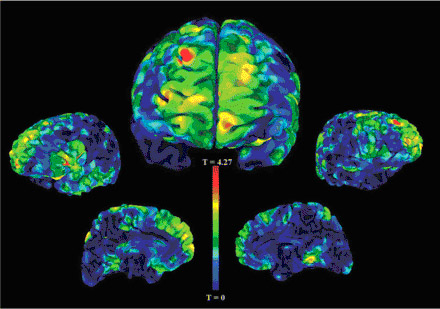

Reduced gray matter (red):

vestige of early developmental insult?

Magnetic resonance imaging (MRI) brain scans revealed that patients with a bedwetting history had reduced gray matter in the front of the brain — which processes information — but the patients without a bedwetting history did not. This part of the brain has been associated with bladder control and with the development of schizophrenia.

Patients with schizophrenia who had a history of childhood bedwetting showed reduced gray matter (the working tissue of the brain) in the front of the brain, particularly an area near the top on the right side (large red area). The frontal areas are known to be involved in bladder control and have also been implicated in schizophrenia, hinting that the childhood problem and attendant structural anomalies may represent a vestige of an early insult to the developing frontal cortex. Structural and functional MRI image data.